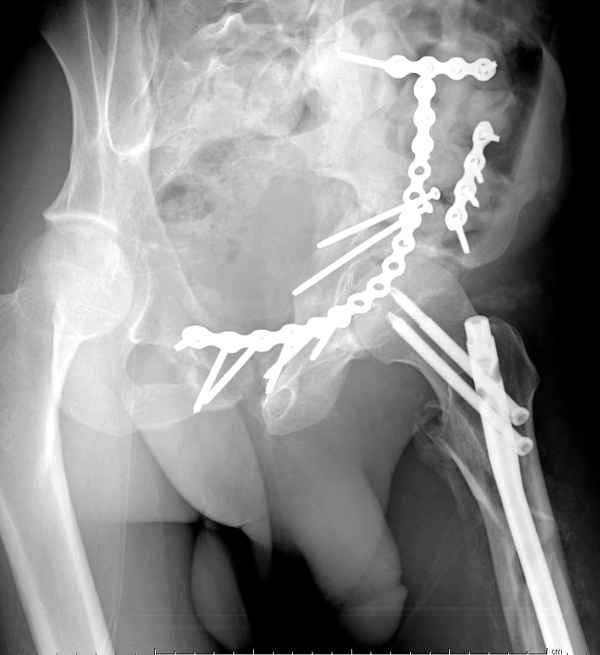

По-моему, надо готовить больного к будущей артропластике, но без опоры на задний столб невозможно удержать протез. Опорная конструкция (кольца и т.д.) должны иметь опору, и поэтому мы бы сделали реостеосинтез задним доступом. При надобности остеотомия и рутинная фиксация с межколонными винтами.

В дальнейшем, время покажет, когда приступить к артропластике....

Здесь несколько вариантов двухколонных свежих переломов, которые были оперированы из одного-заднего, а также из двух: переднего и заднего доступов.